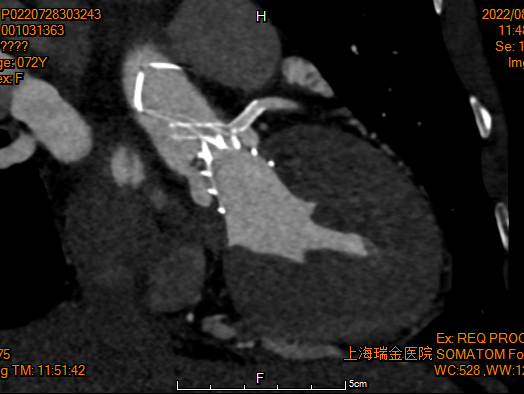

30%收缩期

Annulus

长径: 24.8 mm

周长: 68.6 mm

面积: 352.3 mm²

LVOT

长径: 24.3 mm

周长: 66.3 mm

面积: 321.7 mm²

SOV

27.3 x 25.8 x 25.9 mm

STJ

长径: 27.6 mm

周长: 84.4 mm

面积: 566.2 mm²

高度: 13.8mm

升主动脉

长短径:39.7x37.6mm

(距瓣环40mm)

RCA

下缘高度 10.2mm

上缘高度 11.9mm

瓣叶长度 12.7mm

LCA

下缘高度 7.1mm

瓣叶长度 11.8mm